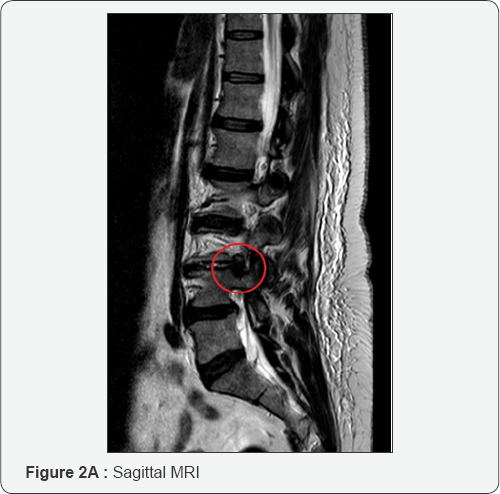

At this point it is necessary to move the endoscope's tip towards the cranial part of the foramen and identify the exit nerve root. This one is within soft tissue like fat and muscles and often it can be quite hard to find it. It is very important to remain with endoscope tip always close against the bony surface. Sometimes it can be useful to identify the upper transverse process which can help in indicating where to look for the exit nerve root: just inferior and medially to it. It is really a matter of a gentle dissection using an endoscopic probe and a coagulation tip. This last instrument, can also be used to identify the exit nerve by stimulating the surrounding soft tissue at a very low voltage. If we touch the nerve we will assist to some kind of motor response of the corresponding leg. Generally the nerve is found to be stretched out by the underlying prolapsed disk. Once the disk is visualized the nerve must be dissected apart and the protrusion removed. It is possible to check when an adequate decompression is achieved just seeing the nerve root moving freely up and down (Figure 2A-2G). At this point, after having checked for any bleeding, the working tube is withdrawn and the skin incision (8mm long) glued.